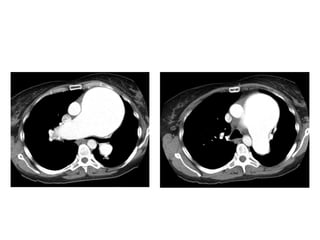

49-year-old woman with persistent and progressive cough, dyspnea, and hypoxemia,

prompting biopsy of her lungs, which revealed chronic desquamative interstitial

pneumonia (DIP) related to extensive cigarette smoking history, CT images through

mid and lower lungs show patchy ground-glass opacities in all lobes of both lungs

with peripheral predilection accompanied by lower lobe bronchial wall thickening, note

small cysts scattered mostly in right lung in regions of ground-glass attenuation,

finding that can occur in DIP